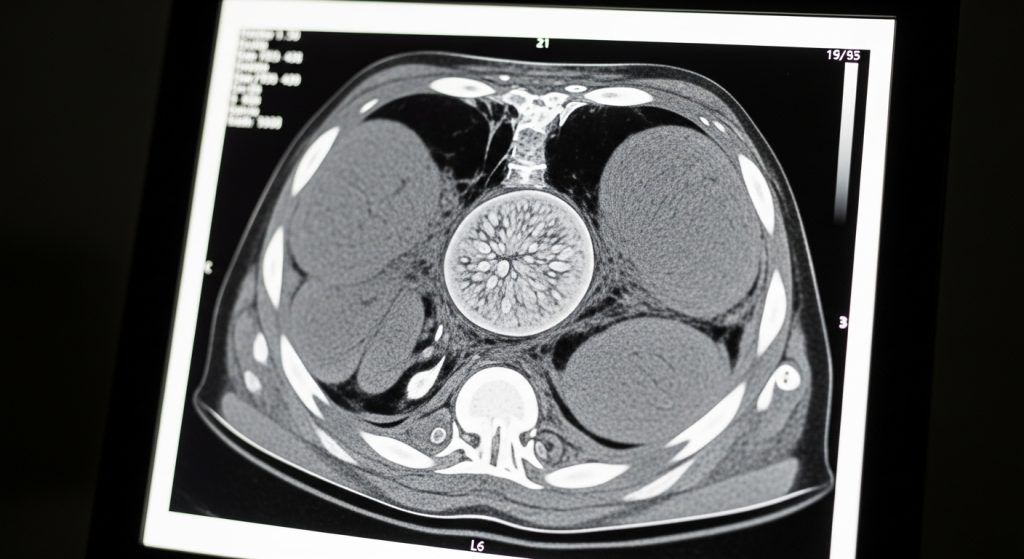

- Imaging (CT, V/Q scan, or other studies): to assess lung structure and evaluate for chronic clots.